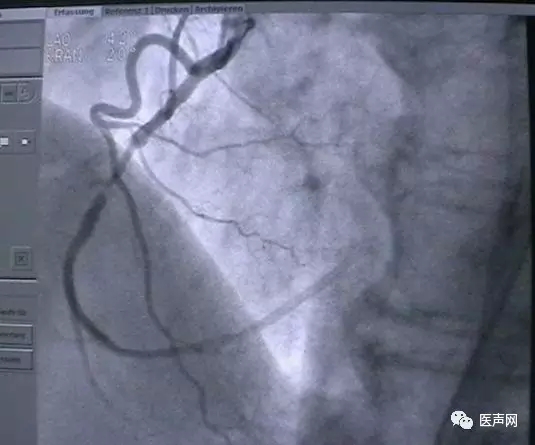

病例3:LAD中段90%狭窄

操作过程:JL4导引导管同轴性不好,支撑力不够,直接支架术(direct stent)有阻力,改用EBU 导引导管---植入TAXCOR 3.0×18mm DES.说明:导引导管的重要性。下图所示: